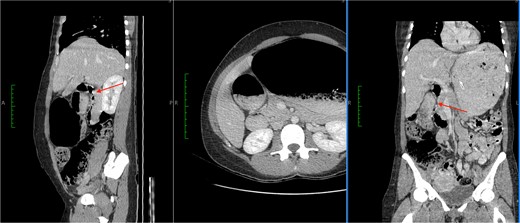

She had emergency admission 6 months prior with a clinical diagnosis of intestinal obstruction. At that time she had presented with significant abdominal distension, abdominal pain, and non-bilious vomiting. An abdominal CT scan was performed during her admission. This showed a dilated stomach with cut-off at the duodenum, but no causative lesion was identified (Fig. 1). She was managed conservatively and discharged, but continued to have intermittent episodes of bloating, pain, and anorexia over the intervening months, though not at a level that required admission.

CT images showed a massively dilated stomach and duodenal cap with a point of obstruction distal to D1 of duodenum (thin arrows). No obstructing lesion was identified.